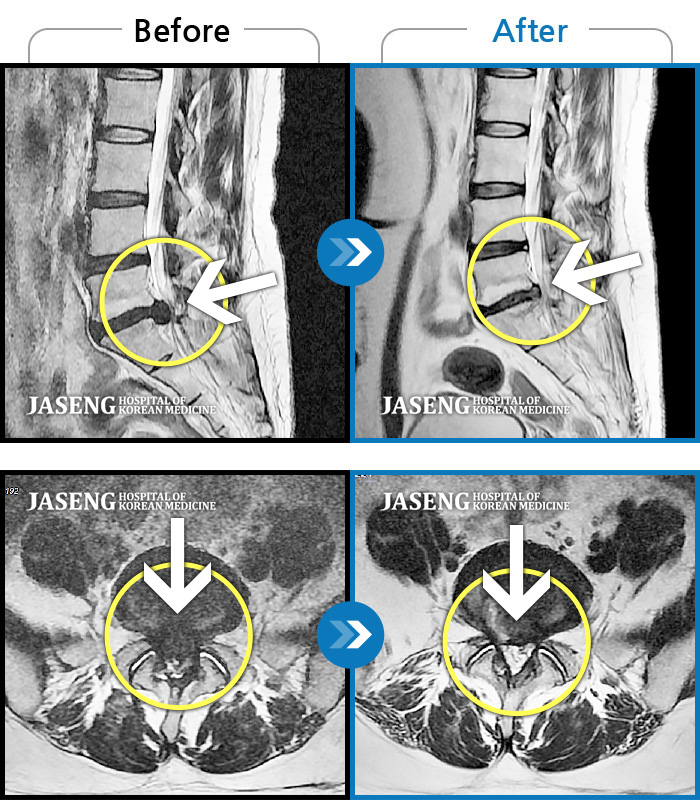

허리디스크

목동 · 고웅 원장

허리통증으로 보행 불가. 우측 다리의 통증과 저림, 화끈거리는 통증과 차가운 느낌 번갈아 나타남

촬영시기

2020.12.18 ~ 2024.11.15

2024.12.24